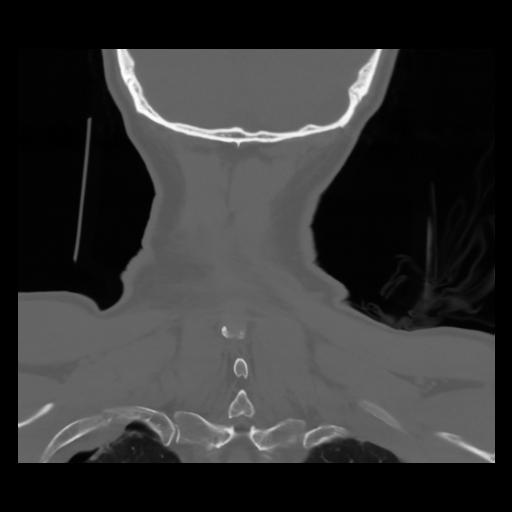

13 P.BLANDAS,,Coronal,2.000,P.BLANDAS,Coronal,